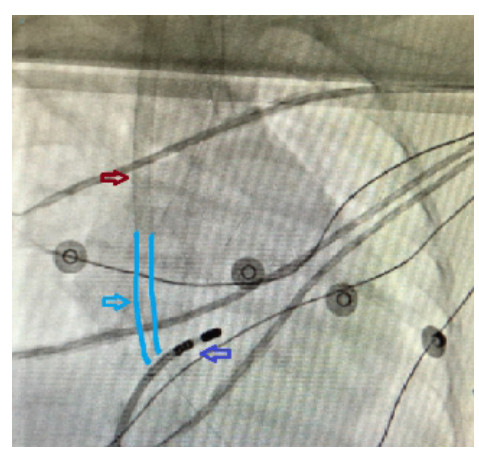

患儿在静脉-动脉ECMO(VA-ECMO)支持下持续发生室性心动过速,先后予胺碘酮13 µg/(kg · min)持续静脉泵注,维拉帕米13.3 mg Q8 h/Q6 h口服,西地兰0.1 mg静推,心率仍波动于170~200次/min之间。多学科会诊讨论后,诊断为:心律失常(室性心动过速);心源性休克;心动过速相关性心肌病;急性重症肺炎;心功能不全。予艾司洛尔负荷量5 mg静推3次,再予30~60 mg/h维持,心室率降至110次/min左右(图 2),患儿于2019-01-17在ECMO支持下行心电生理检查加射频消融术。操作过程:手术经右股静脉穿刺,在ECMO抗凝下给予肝素1 mg/kg。心率维持118~131次/min,血压维持在61/45 mmHg~88/80 mmHg之间,维持不理想,在ECMO运转下继续观察35 min,待患儿心率稳定于84次/min,血压103/86 mmHg,停ECMO运转。置入8F外鞘,导管依次进入右心房、右心室(图 3、4)。行术前电生理检查示:QRS宽大畸形,房室分离,室性心动过速,心率140。应用7.5 F蓝把费冷盐水大头消融导管,在三维标测系统(CARTO)标测下重建右心室激动顺序图,于间隔侧乳头肌处标测到最早双极电位提前QRS 15 ms,单极图呈QS型,且下降支有切记。温控法55℃,功率40 W放电10 s后心动过速即终止,巩固至180 s,观察20 min,未见心动过速发作。术中因ECMO系统形成的右心房负压对射频消融术的影响暂停ECMO 3次。患儿经ECMO支持下行射频消融术后心率、心律恢复正常,当日逐步停艾司洛尔静脉用药。术后第2天撤除ECMO,第4天撤离呼吸机。ECMO撤离1 d后出现室性早搏;撤离4 d后频发室性早搏,给予索他洛尔、普罗帕酮、卡托普利治疗心律失常。2019-01-22转入心血管内科,期间有间歇性心律不齐发作。2019-02-13再次出现室性心动过速,于外院救治。随访患儿情况,家属诉患儿循环稳定,再次行心电生理检查加射频消融术,恢复窦性心律,5 d后出院。

| 红色箭头所指管道为ECMO静脉插管;浅蓝色箭头所指手绘浅蓝色管道为ECMO静脉插管未显影部分;深蓝色箭头所指为射频消融导管头端 图 3 导管入右房时的X线影像 |